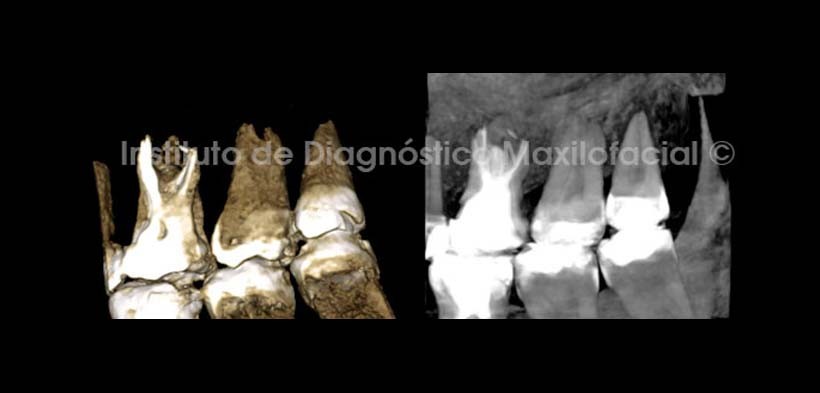

En cortes transaxiales de la pieza 2.6 (Fig. 4), se muestra la amplia zona de rarefaccion y la erosión del piso del seno maxilar en relacion con la raiz palatina, así mismo se observa una imagen hipodensa a nivel del tercio medio de esta, probablemente correspondiente a un proceso de reabsorcion radicular interna. Además se evidencia la deficiente obturación de los conductos radiculares. En la Pieza 2.7 (Fig. 5) se observa la restauración coronaria junto a una lesion cariosa recidivante amplia y profunda con aparente compromiso pulpar. Nótese el acortamiento de la longitud radicular, la ausencia de constriccion cervical y la ampliación de la camara pulpar en sentido ocluso-apical, Signos tomograficos correspondientes a anomalía de la morfologia dentaria sugerente de Taurodontismo.

En las reconstrucciones tridimensionales (Fig. 6) se observan los signos tomográficos descritos en las imágenes anteriores de forma mas ilustrativa.